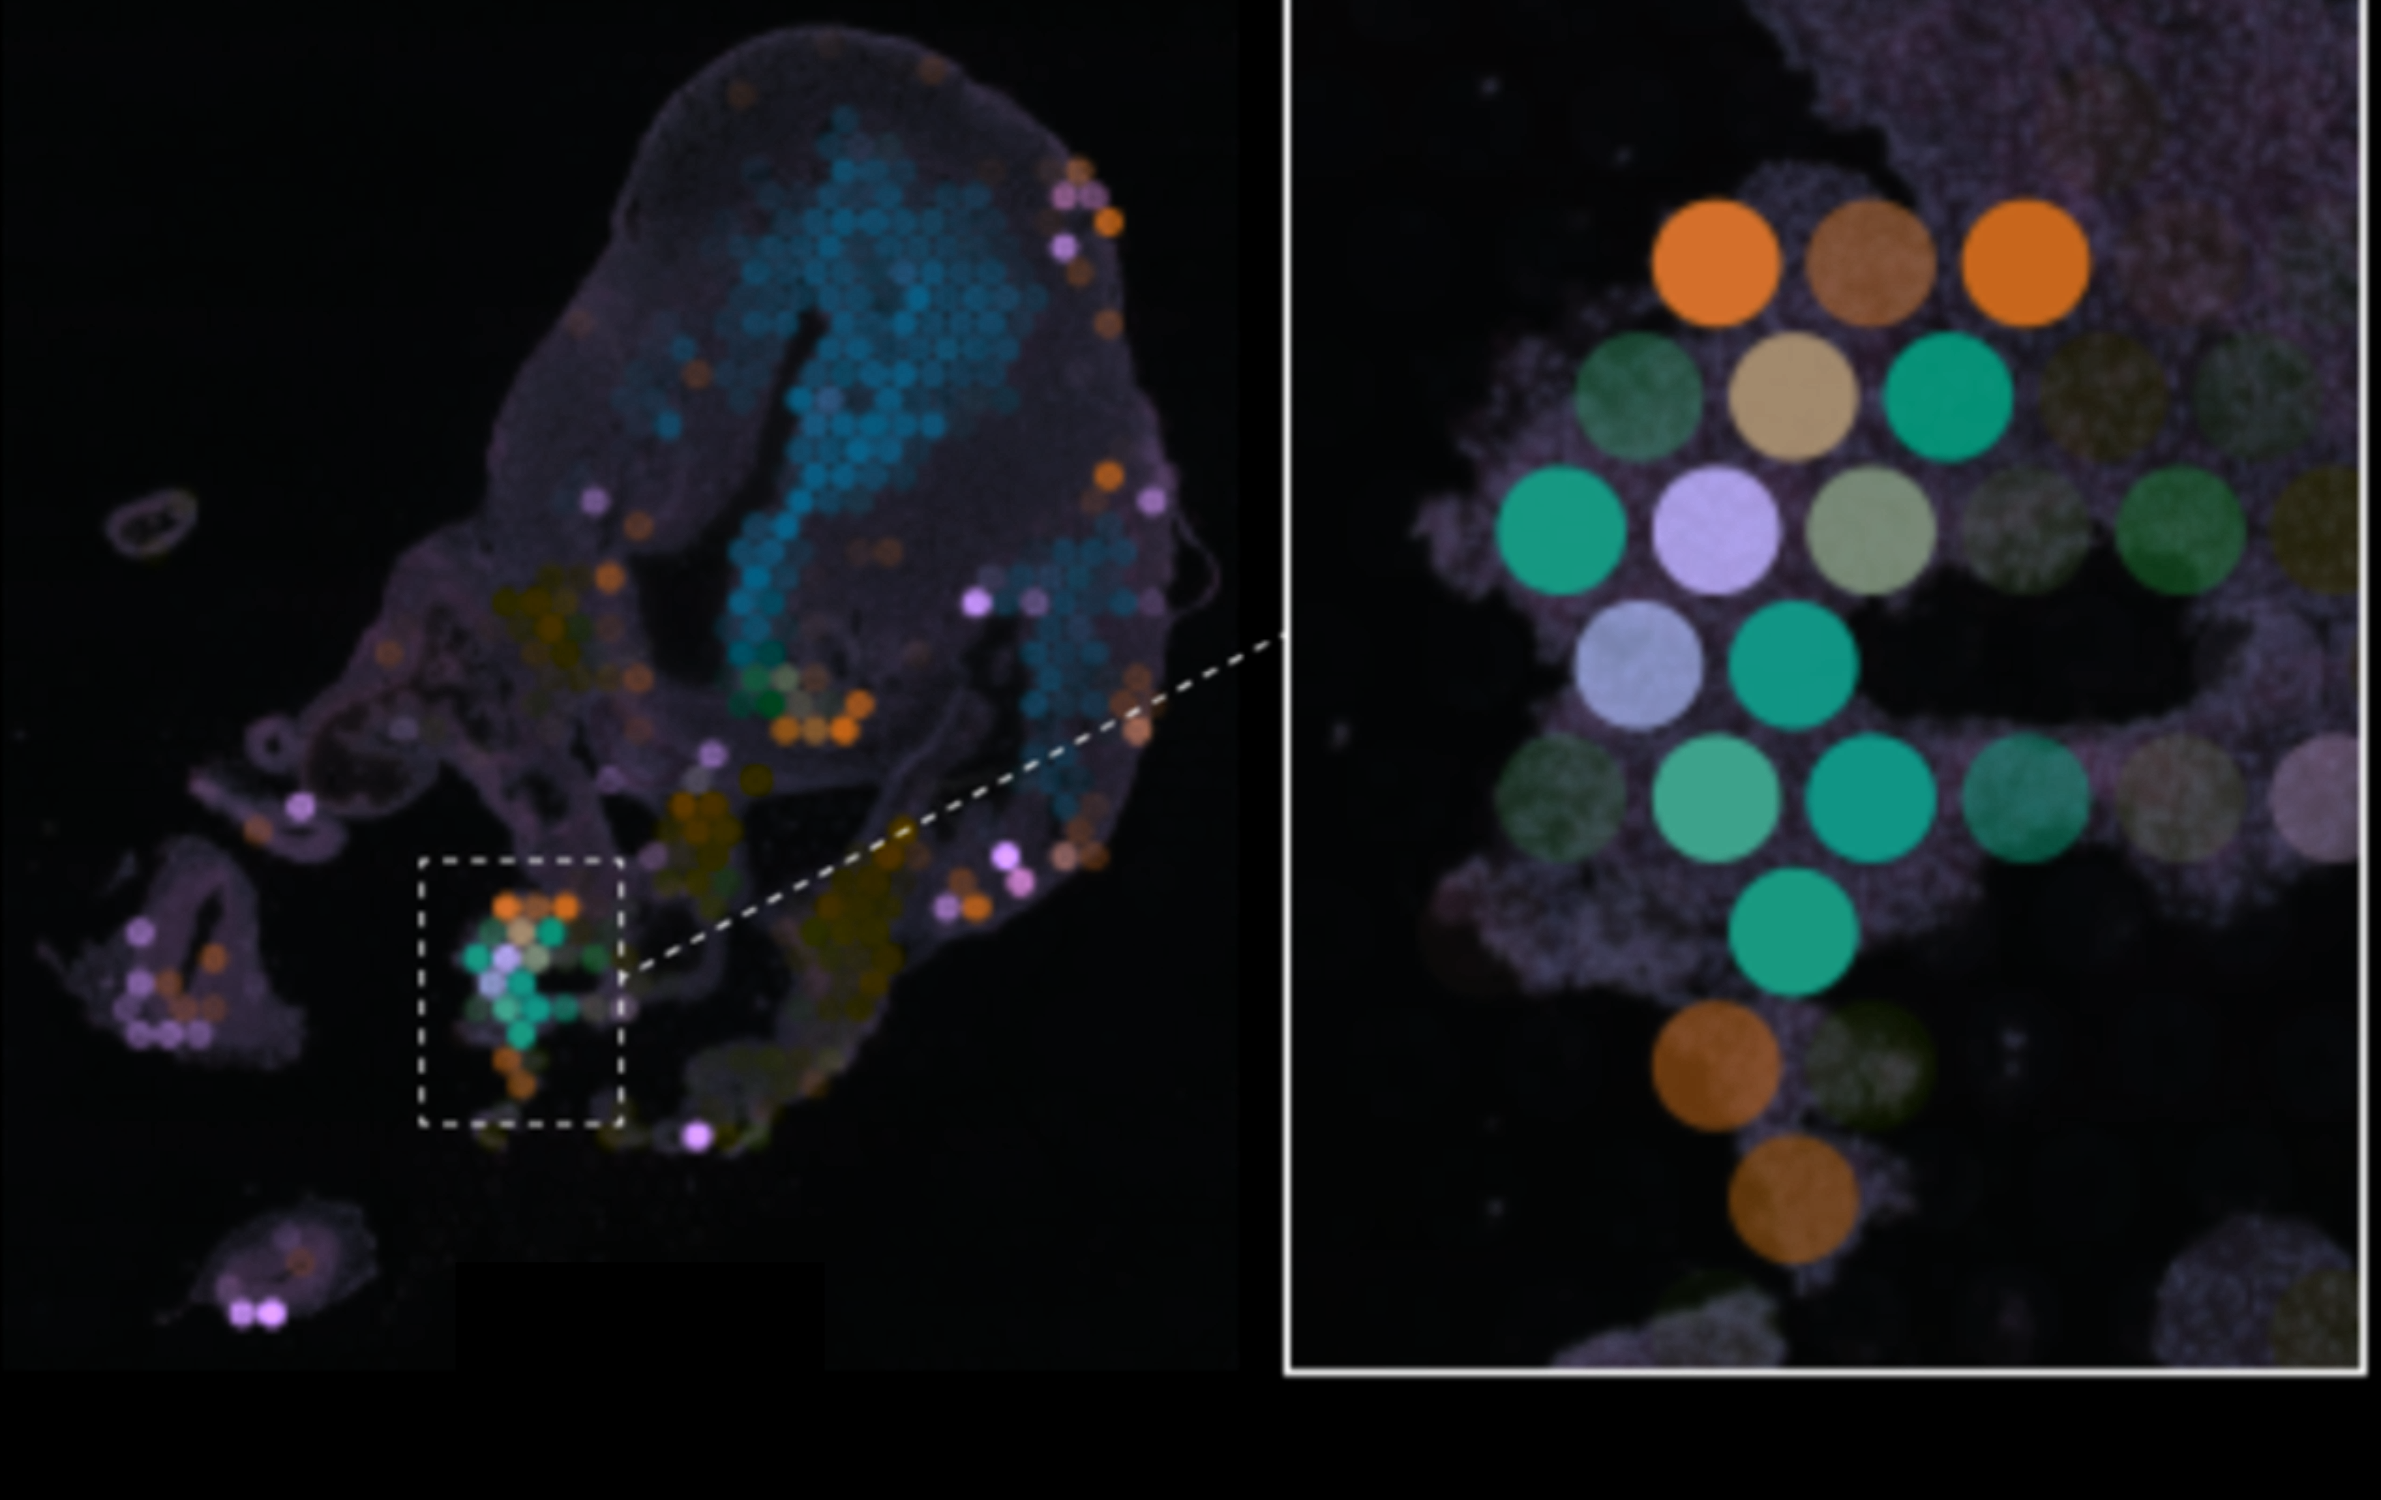

Cells come together to form cardiac niches

The heart forms through many different events. These are thought to happen because of different types of cells coming together to form communities and neighbourhoods that we call niches. Within these niches, the cells are talking to each other, influencing their neighbour’s movements and maturity to build tissue-level structures such as blood vessels or functional muscle.

How we piece the heart together

Our expert researchers use many complementary techniques and methods to solve the mysteries of cardiac development. From animal models and experiments to machine learning and big data, the CellTalk-HHD consortium coordinates its approach across the institutes involved to triangulate on the communication taking place within the growing tissue.